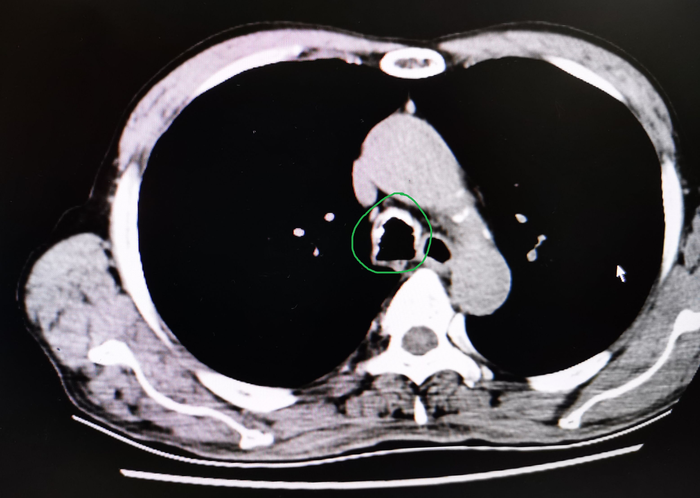

患者男,68岁,因“咳嗽伴发热15天“入院。

辅助检查:血常规正常。胸部CT报告:1、右肺上叶少许炎性灶伴局部支气管轻度扩张;2、右肺中叶偏小伴少许不张,请结合支气管镜;3、右肺中叶、左肺散在炎症;4、右肺上叶、左肺下肺囊肿;5、冠脉钙化。

为了进一步明确,我们做了支气管检查,镜下发现支气管出现“惊奇”的一幕——气管、支气管黏膜下有多发性骨质或软骨组织结节状增生并突向管腔。

图12

看到这种病变是不是觉得很惊奇?能看出这是什么病吗?其实,这种病变常见于“骨化性气管支气管病”“气管支气管淀粉样变”等少见病。

我们再回看这个胸部CT的纵膈窗可以发现气管明显有气道壁后方膜部不受累的环状高密度影(钙化灶)。

图13

因为慢性气管支气管炎、老年性气管支气管等情况也可出现类似改变,很多人感觉司空见惯或认识不足常常不注意而漏诊。

我们在支气管镜下行活检,病理回报符合“骨质沉着性气管病”——即“骨化性气管支气管病”诊断成立。

图14